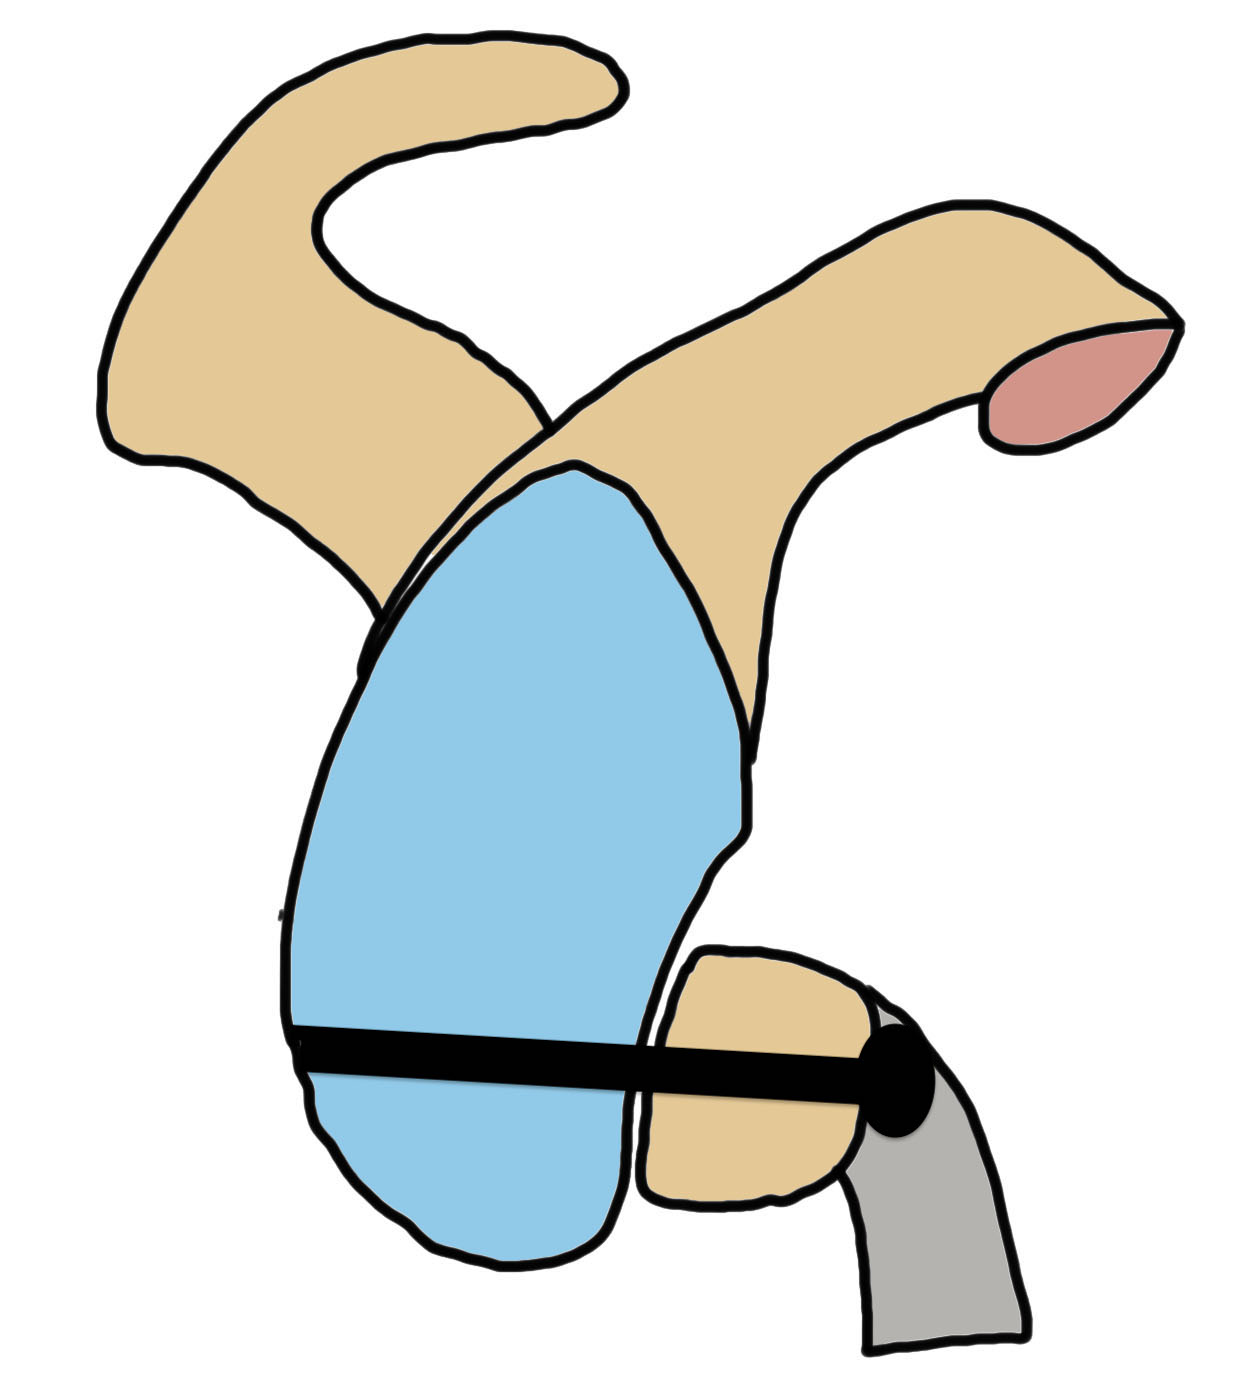

Bone block positioning

Concepts

- coracoid must not overhang medial to avoid osteoarthritis

- coracoid < 5 mm medial to glenoid rim

- coracoid lower half of glenoid 2 - 5 o'clock

- fixation screws purchases posterior glenoid cortex

- screws do not penetrate articular surface

Traditional Latarjet v Congruent arc

- align concave inferior surface coracoid with medial concave glenoid

- graft is thinner in this position, making screw fixation more difficult

Graft malposition

Screws and graft too medial

Bone graft too medial

Coracoid graft too superior on glenoid